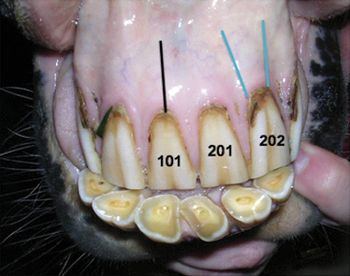

Discover why this feline is missing a canine.

It is important to be able to identify oral pathology and anomalies. It is equally important to correctly record the pathology on dental charts. A thorough dental examination includes both conscious and anesthetized examinations as well as charting disease processes, pathology and anomalies, and treatment plans.